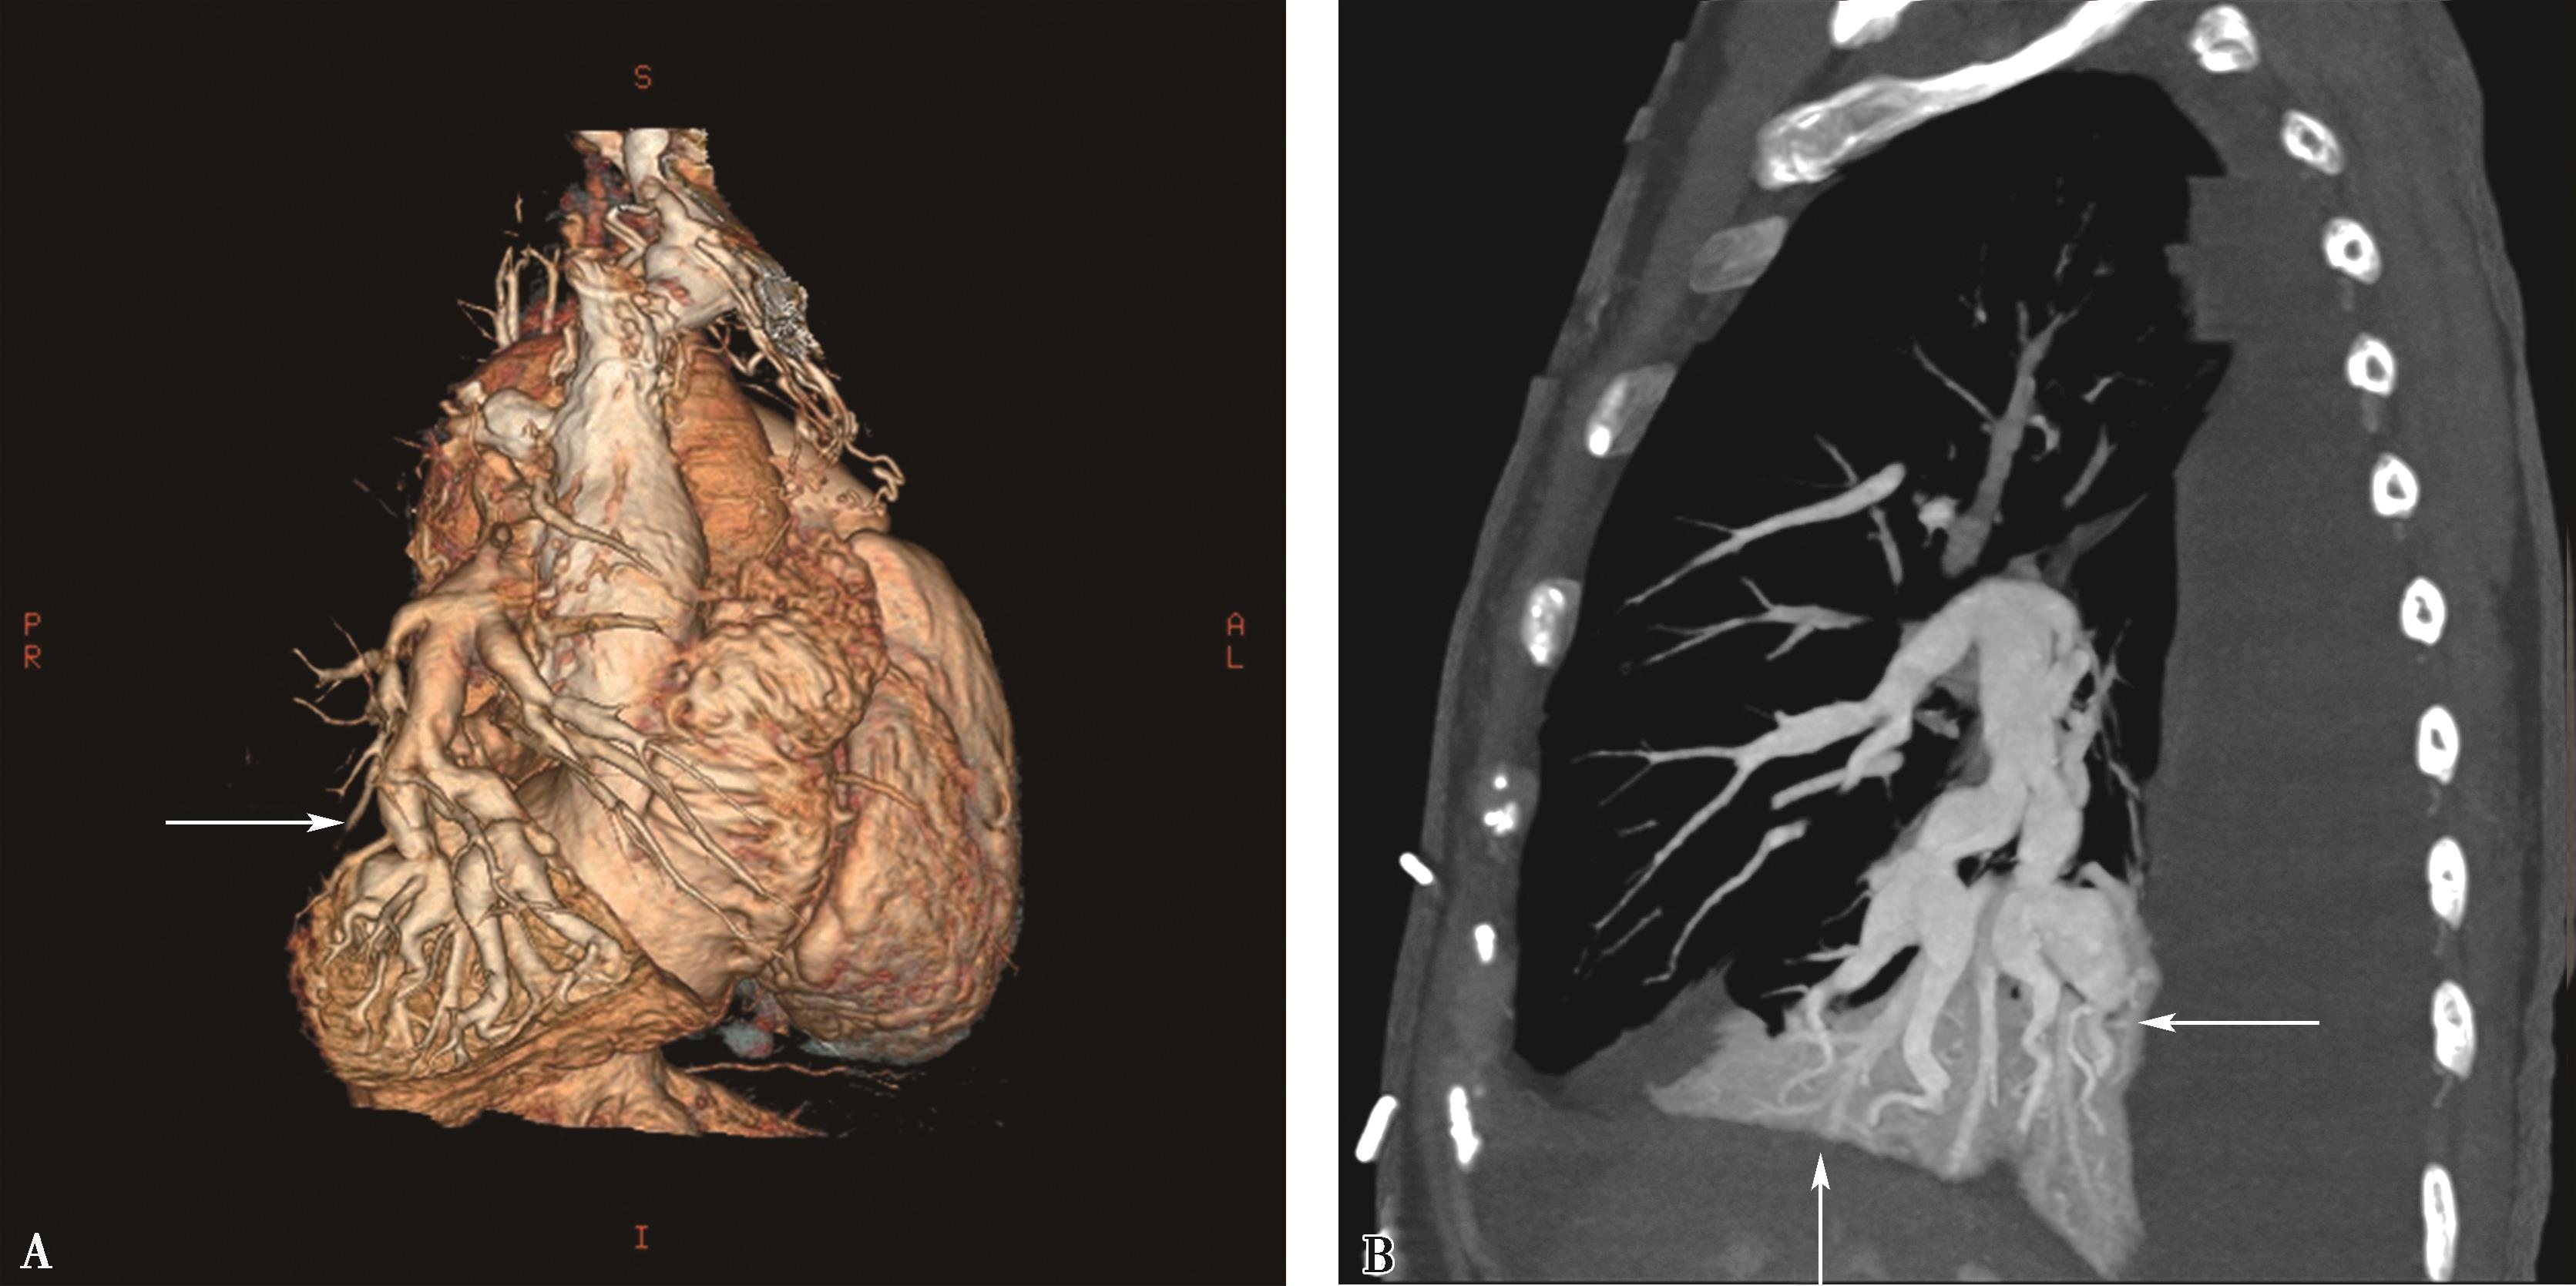

图8-7-1 女,21岁,反复咯血2年,胸闷气短1年半

CT横断扫描。A、B.多层重组;C、D.示主肺动脉及左右肺动脉内结节状充盈缺损,可见 “指压征”(↑),右肺动脉及左下肺动脉闭塞;前上纵隔中等密度影,考虑为纵隔转移(A▲)。肺动脉造影(E)示主肺动脉不规则充盈缺损,右肺动脉及左下肺动脉闭塞,术后病理诊断:低分化平滑肌肉瘤(F)

1.直接征象(图8-7-1~图8-7-3)

(1)主肺动脉或单侧肺动脉干管腔充盈缺损,大块状充盈缺损呈分叶、结节样(指压征),可以延肺动脉血管长轴向远侧蔓延。

(2)晚期肿块沿肺动脉长轴管腔膨胀性生长,可以充满主肺动脉、左右肺动脉干及叶段分支管腔,血管闭塞。CTPA检查对比剂存在于节结间呈分隔状,有一定提示。

(3)肿瘤可以发生于或累及肺动脉瓣、右心室流出道。如果有蒂存在,肿瘤可以有一定活动度。

(4)肿瘤依恶性程度,生长发展较快,肺门血管影圆隆增大,呈 “三叶草”征。

(5)远处转移:最常见的为肺和肋骨。

2.间接征象

(1)肺动脉扩张,右心房室增大,肺动脉高压。

(2)双肺实质灌注不均。